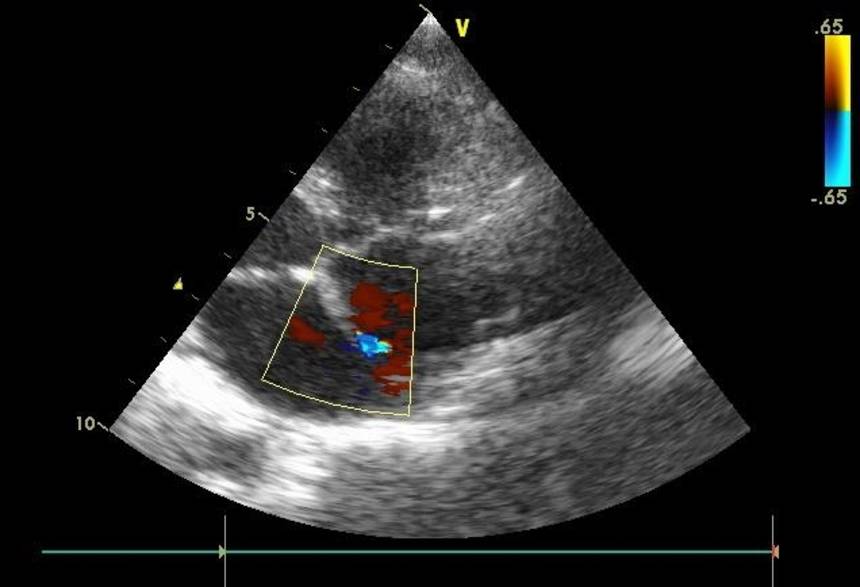

Эхокардиография

ЭхоКГ позволяет обнаружить анатомические составляющие тетрады Фалло.

- Эхо-КГ (основная методика — позволяет увидеть морфологию порока и определить функциональное состояние сердца).

- Допплер-эхо-КГ (позволяет определить направление тока крови — выявить регургитацию и турбулентность).

При диагностике используют рентген и ЭХО-кардиографию, ФКГ, ЭКГ, клинический анализ крови. Среди специальных методов исследования при подозрении на ВПС у детей – ангиография и зондирование сердца.

Эхокардиография – метод кардиологического обследования, который дает детальную информацию о характере сердечных аномалий и внутрисердечной гемодинамике. раньше вместо этого метода применялась катетеризация сердца. Этот метод не применяется изолировано, его нужно сравнивать с результатами ФКГ, ЭКГ и пр.